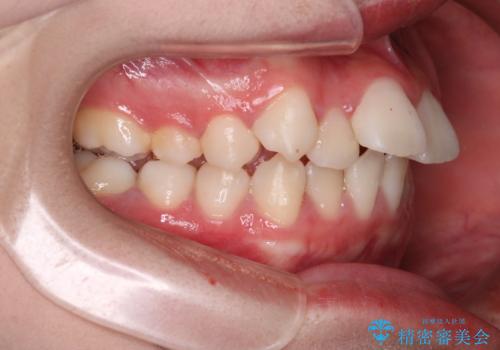

- 前歯の叢生と突出感を主訴に来院されました。

抜歯をしてワイヤー矯正を行いました。

上顎両側小臼歯を抜歯して治療を行い、突出感も大幅に改善しました。